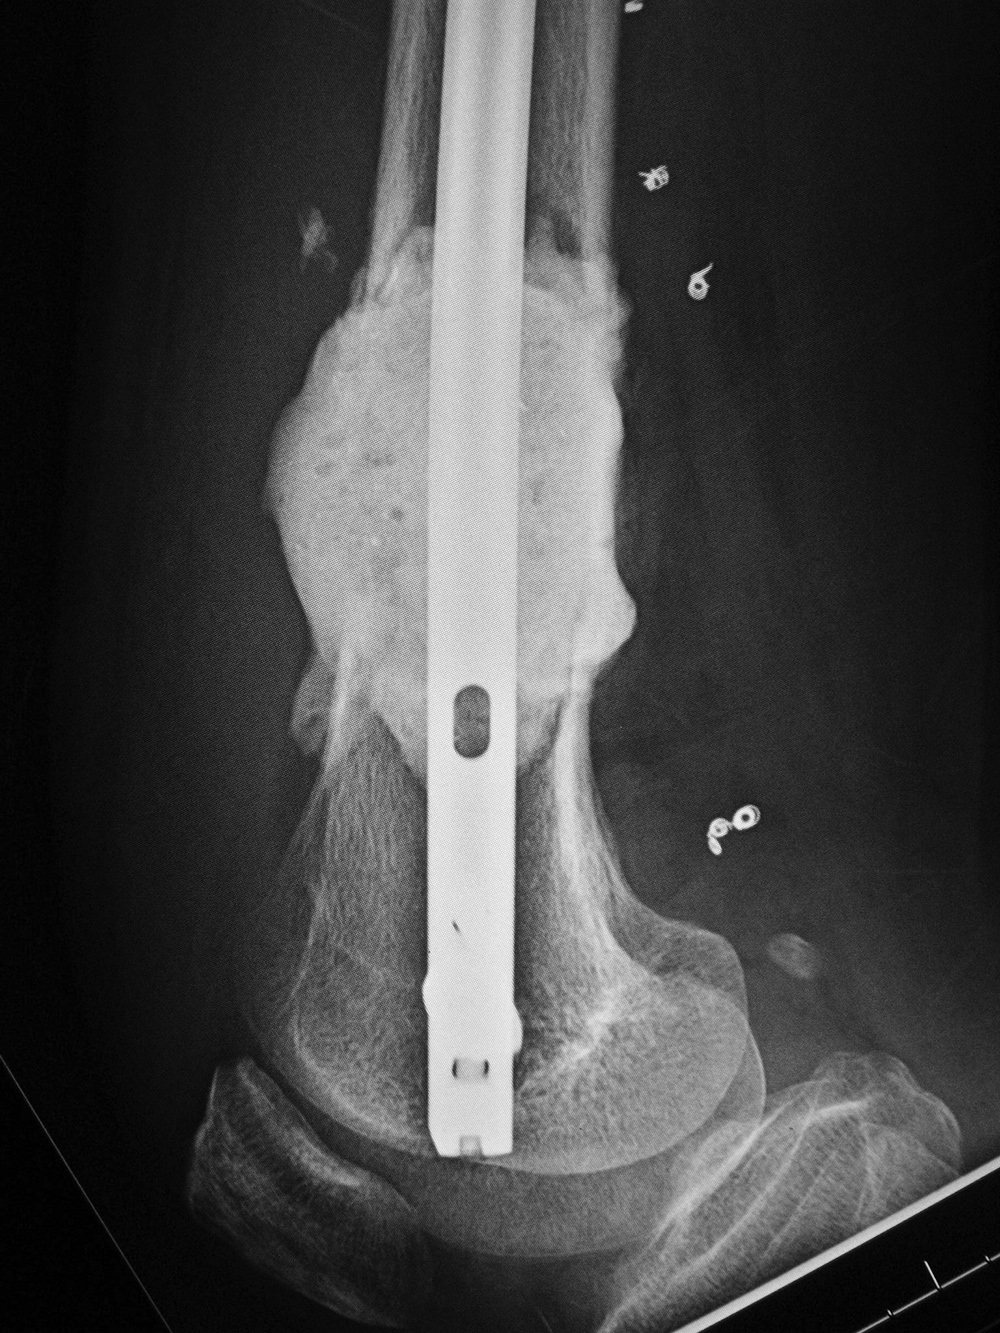

43 year-old man with comminuted right tibia and fibula fractures as well as extensive bone loss and soft tissue injury. A tibial intramedullary nail with proximal and distal locking screws is present as well as multiple rounded bony allografts. There are also large skin staples.